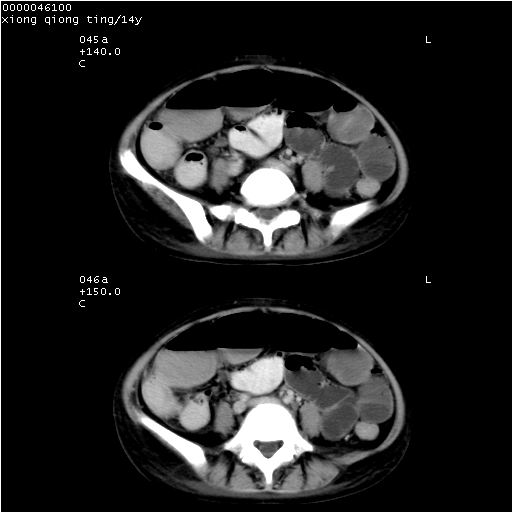

中下腹及盆腔ct轴位平扫+增强扫描(层厚10mm,螺距1.0,重建间隔10mm),图像如下:

(注:患儿检查当日上午9时口服胃肠道对比剂,下午3时许行ct扫描检查,未行对比剂直肠保留灌肠,检查当日患儿腹泻)

考虑结核性腹膜炎并不完全性肠梗阻可能性大(1肠管积气扩张.2.腹膜厚淋巴结肿大.3盆腔积液.)

中下腹及盆腔ct轴位扫描(ps+ce)提示:腹部肠管明显充气扩张,并见数个不同宽度之气液平面;疑不全性肠梗阻或肠郁张。临床会诊考虑为患儿腹泻,肠郁张所致;后来未经特殊处理,患儿大便恢复正常,亦无腹胀。

临床出院诊断:1)结核性腹膜炎。2)腹膜后淋巴结结核。3)脂肪肝。